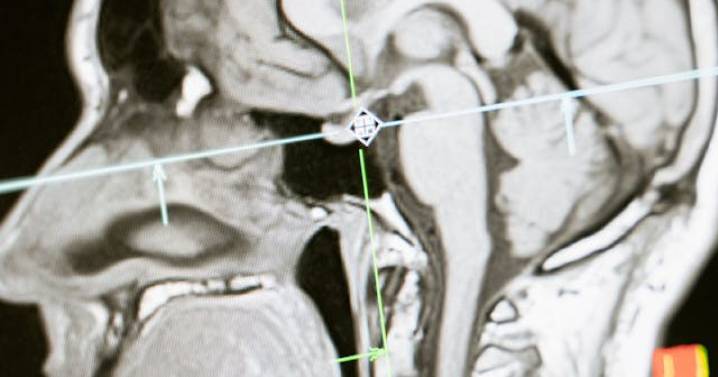

La investigación, dirigida por neurocientíficos de la Universidad británica de Cambridge, se basa en datos de resonancias cerebrales de 3 mil 802 personas de entre 0 y 90 años, en las que se han mapeado las conexiones neuronales mediante el seguimiento del movimiento de las moléculas a través del tejido cerebral.

En la primera etapa de la infancia hasta la niñez, de los 0 a los 9 años, el volumen de la materia gris (que contiene las neuronas) y de la materia blanca (que contiene las conexiones)